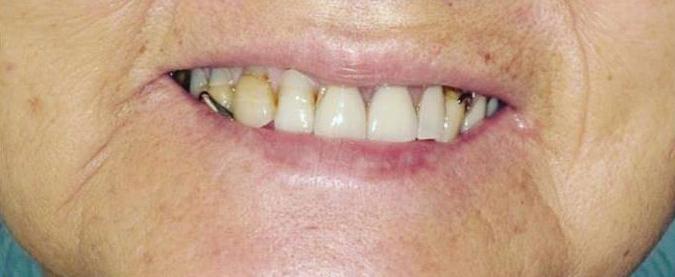

11 | Do I Need A Periodontist? | By Karl A. Smith, DDS, MS 12 | Your One-Stop Solution For a Healthy Smile | Submitted By Total Dental Care 13 | Chiropractic and Exercise For Optimal Health | By Alicia Kovach, DC 13 | Can Burn Wounds Bleed? | By Paul Samakow, Attorney 14 | TMJ Disorder and Exercise | By Jeffrey L. Brown, DDS 16 | All-On-Four Dental Implants | Submitted By Sivakumar Sreenivasan, DMD, MDS

18 | Discover Your Perfect Full Arch Dental Solution | By Judy Yu, DMD, MBA

Discover Your Perfect Full Arch Dental Solution

Embrace Comfort and Affordability

In the past, individuals missing multiple teeth had limited options beyond uncomfortable and ill-fitting dentures. However, with the introduction of dental implants, removable dentures have become a viable choice. Although dentures may require adhesives and fall short of replicating the natural form and function of teeth, they offer affordability and easy removal for cleaning.

Four Implant Overdenture

Secure and Functional

Your dental arch, whether on the top or bottom, plays a crucial role in your oral health. When the majority of your teeth are missing or reach a point where replacement is recommended, a full arch replacement becomes necessary. Fortunately, there are more options available now than ever before for comprehensive full arch treatment.

Removable Dentures

Stabilized overdentures resemble traditional removable dentures, but with a significant improvement in stability. By utilizing four locators on the underside of your denture plate, they securely attach to implant abutments. These snap-on dentures eliminate rocking, shifting, or rubbing, as the implants keep the appliance firmly in

Please see “Full Arch,” page 61